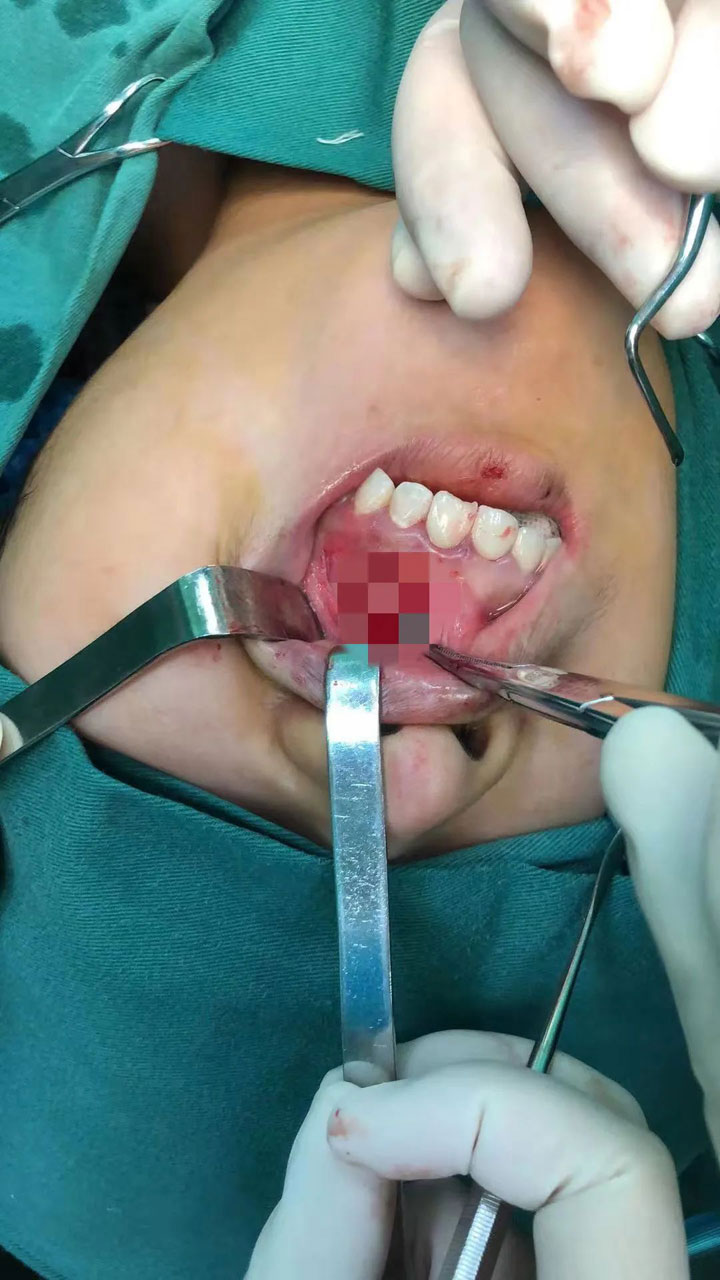

患者高某,20岁,一年前发现左上前唇侧牙龈隆起,一周前拍摄CBCT提示:左上颌骨有一囊肿可能。2021年8月2日,口腔科王健副主任接诊,考虑到患者还是学生,时间比较紧张,遂决定启动“日间手术”。所谓“日间手术”,就是患者提前在门诊做好住院手术所需的各项检查及准备,预约手术时间,住院到出院在1个工作日内完成。2号当天高某在门诊将术前检查完善,并预约好4号入院。8月4日下午,在局麻下行“左上颌骨囊肿刮治术+21、22根尖切除术”,手术十分顺利,患者安返病房。

8月5日上午,在查房结束后,王健副主任给高某进行术后检查:切口愈合良好,他嘱咐患者保持口腔清洁,术后7--10天来医院拆除缝线。8点43分,患者出院。高某母亲高兴地表示:“一直以为手术治疗需要住院好几天,孩子上学真没时间,多亏王主任给咱们安排这个日间手术,不仅省时间精力,还能医保报销,真是好!”